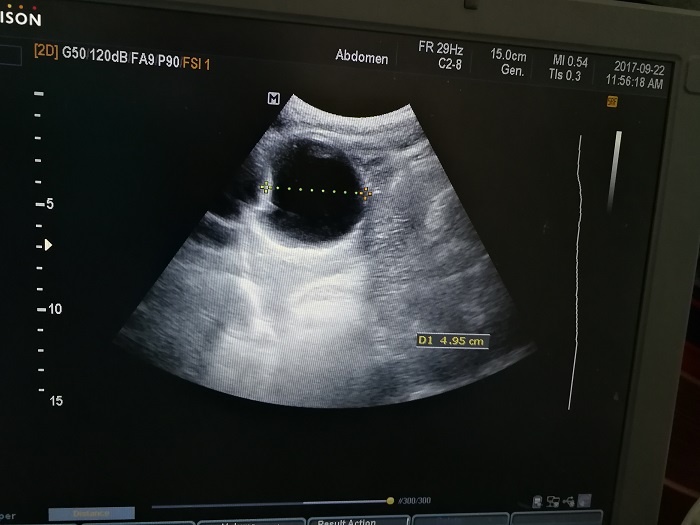

扎西(化名),男,15歲,包蟲病篩查陽性,牧區(qū)孩子,家里有牦牛20頭、羊200只,狗1條,牛羊自家屠宰,飲用河水。

●革吉縣初級(jí)中學(xué)篩查點(diǎn) · B超現(xiàn)場(chǎng)圖片

除了包蟲病篩查外,連續(xù)三天的學(xué)校體檢我醫(yī)療隊(duì)發(fā)現(xiàn)腎積水、腎囊腫、腎結(jié)石的學(xué)生患者較多,我們將體檢到的相關(guān)臟器疾病同時(shí)間反饋給了班主任,讓他們密切觀察病情,及時(shí)通知家長。劉冬梅醫(yī)生建議,學(xué)校要組織學(xué)生多飲水,同時(shí)多加觀察本地水質(zhì)情況。

本次篩查,革吉縣初級(jí)中學(xué)共篩查學(xué)生498例,陽性3例,疑似2例。